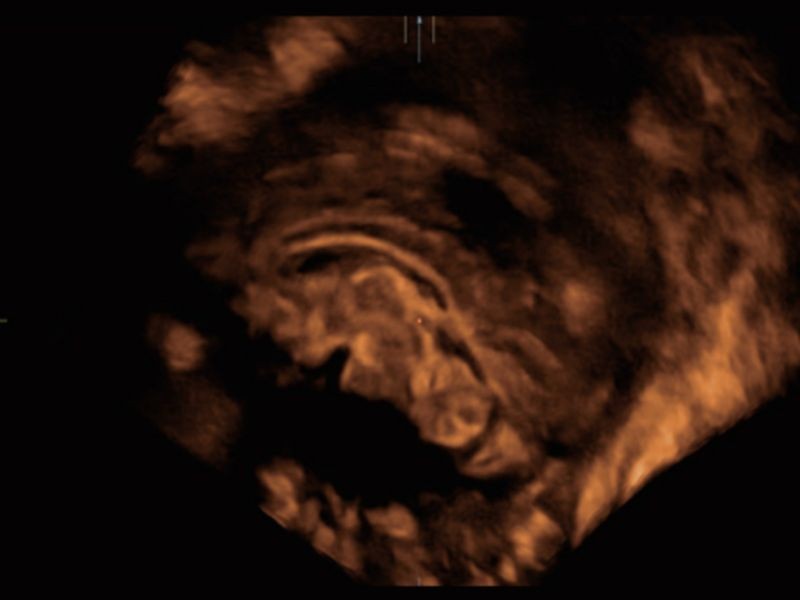

Realismo e clareza sem precedentes - iLive com Hyaline

Ao imitar múltiplas fontes de luz de intensidade variável, o iLive ajuda a melhorar significativamente a resolução anatômica detalhada tanto para estruturas superficiais quanto internas por meio de renderização de volume de alta velocidade.